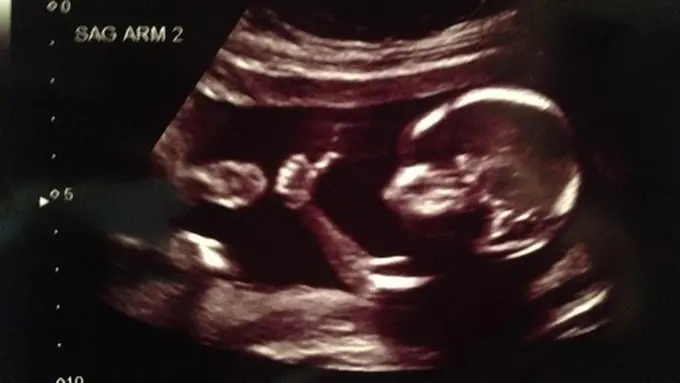

Seorang suami yang menggunakan social media Reddit memposting foto hasil USG terbaru istrinya. Ia menggunakan nama akun meancloth. Ada yang unik dari janin tersebut yang membuat foto ini dilihat secara masif hingga 2,2 juta kali dalam 4 hari saja.

Bila seringnya janin dalam kandungan tampak menghisap jempolnya, janin yang satu ini tampak cukup 'funky'. Ia mengacungkan jempol, seolah sedang memberikan kode pada ibunya, "Aku baik-baik saja, Bu. Sebentar lagi kita akan bertemu. See you, later."

Foto itu terkesan lucu, mengesankan dan membuat banyak calon orang tua merasa terharu. Dengan bahasa tubuhnya yang unik dan tertangkap kamera USG, janin ini bahkan sudah populer sebelum dia lahir. Well, sepertinya kedua orang tuanya cukup bahagia selama menantikan kehadirannya. Kode Baby A di atas menandakan bahwa mereka akan memiliki bayi kembar.